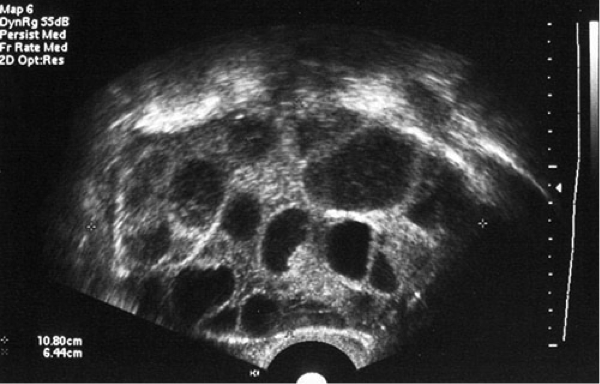

STEP 2 - OVARIAN STIMULATIONS

After 2 weeks of treatment to suppress your ovaries, a fertility hormone is given, again in the form of a daily injection for between 10 and 12 days. It increases the number of eggs you produced compared to naturally where there is only one egg. On average, between 5 to 10 eggs are produced from the treatment. Your doctor may cancel your treatment if you under response to treatment producing less than 3 eggs or over response to treatment producing lots of eggs causing a complication called ovarian hyperstimulation syndrome (OHSS).

STEP 3 - THE TRIGGER SHOT

Your doctor will then monitor you to around 34 to 38 hours before your eggs are due to be collected. You will be given a final hormone injection that helps your eggs to mature. Your doctor will decide the timing of the trigger shot depending on the size and number of your follicles and the level of your estrogen in your blood.

For the egg collection you will be sedated and your eggs are collected using ultrasound as a guide.

A needle is inserted through the vagina and into each ovary. The eggs are then collected through the needle.